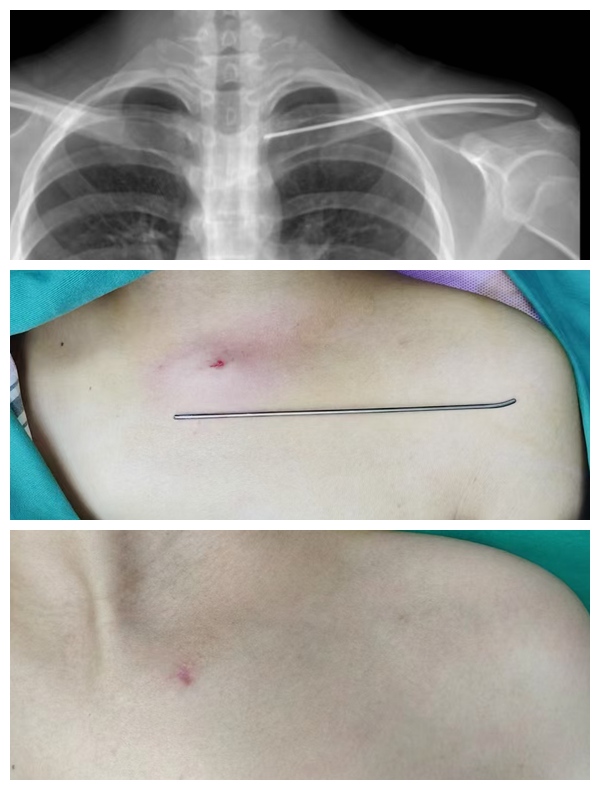

寒假微创取钉“忙” 海南中德骨科医院“隐形”手术守护青少年健康成长